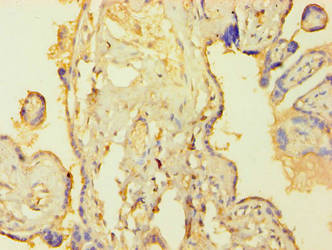

Immunohistochemistry of paraffin-embedded human placenta tissue using CSB-PA618010LA01HU at dilution of 1:100